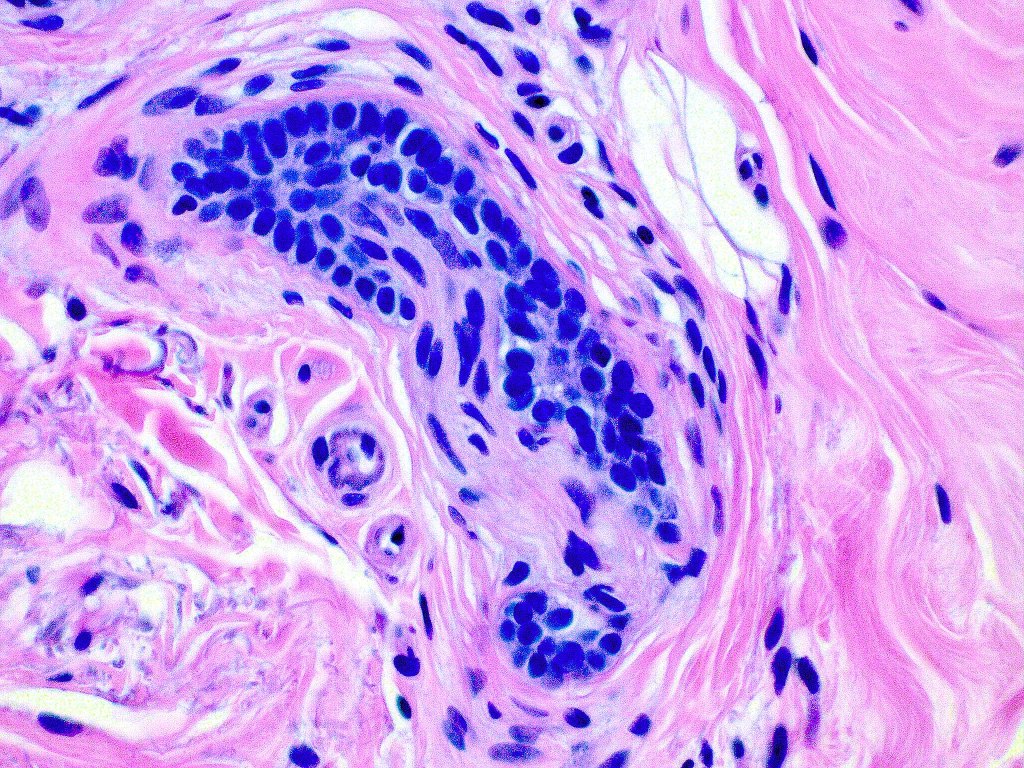

Histological features

•Consists of narrow epithelial strands & keratocysts embedded in a dense stroma

•Epithelial stands may arise from follicular epithelium

•Perineural infiltration is documented but is exceptional & makes differentiation from MAC difficult